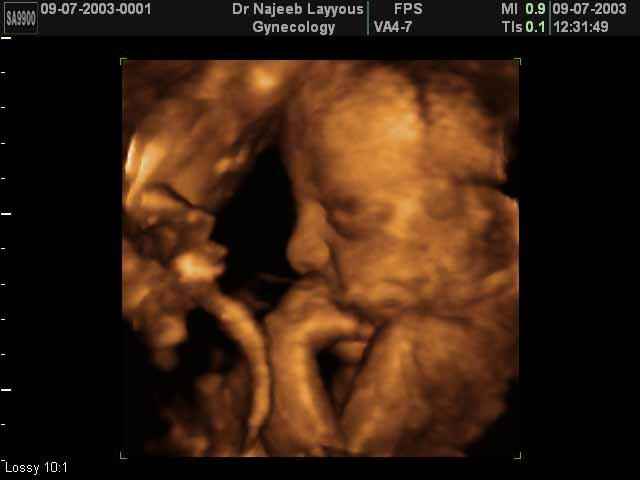

صور جانبية لرأس الجنين بجهاز الالتراساوند ثلاثي الأبعاد | الدكتور نجيب ليوس